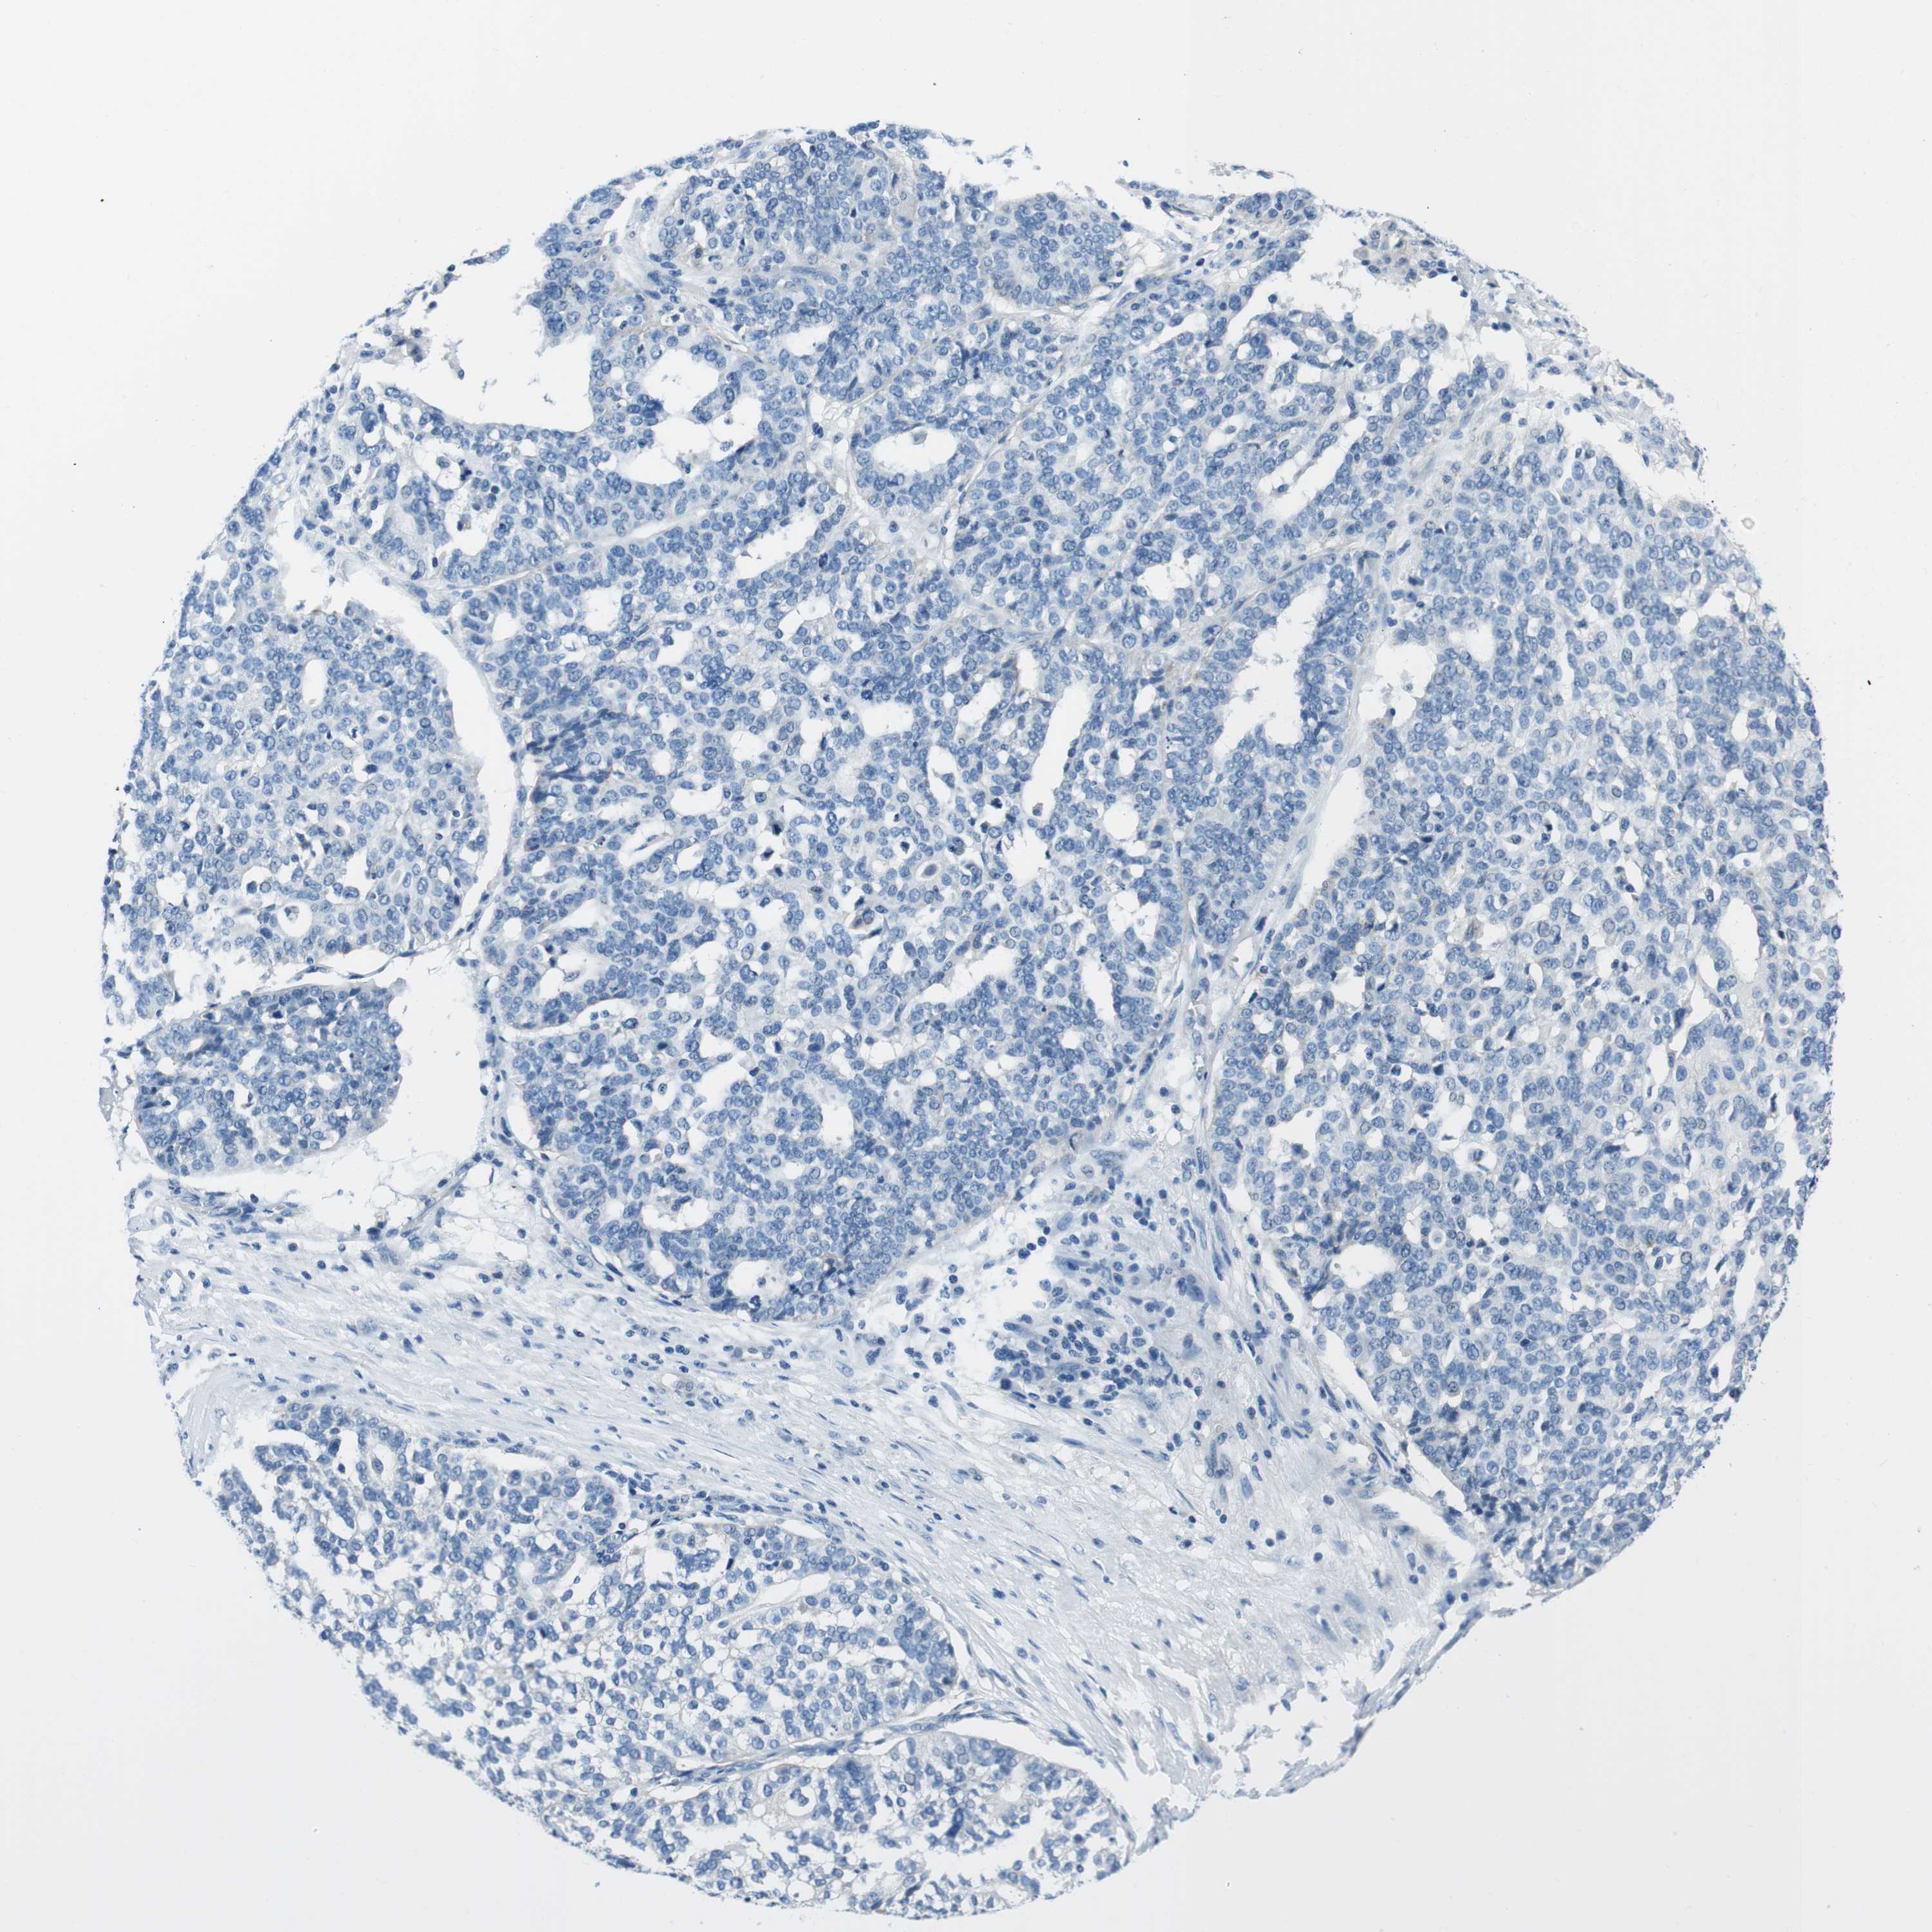

OVARIAN CANCER - Protein expressioni

A mouse-over function shows sample information and annotation data. Click on an image to view it in a full screen mode. Samples can be filtered based on level of antibody staining by selecting one or several of the following categories: high, medium, low and not detected. The assay and annotation is described here.

Note that samples used for immunohistochemistry by the Human Protein Atlas do not correspond to samples in the TCGA dataset.

Antibody stainingi

Antibody staining in the annotated cell types in the current human tissue is reported as not detected, low, medium, or high, based on conventional immunohistochemistry profiling in selected tissues. This score is based on the combination of the staining intensity and fraction of stained cells.

Each image is clickable and will lead to virtual microscopy that enables deeper exploration of all samples and also displays staining intensity scores, fraction scores and subcellular localization as well as patient and tissue information for each sample.

Antibody HPA007845

Antibody HPA026823

Antibody CAB015170

Staining

High

Medium

Low

Not detected

Cystadenocarcinoma, serous, NOS